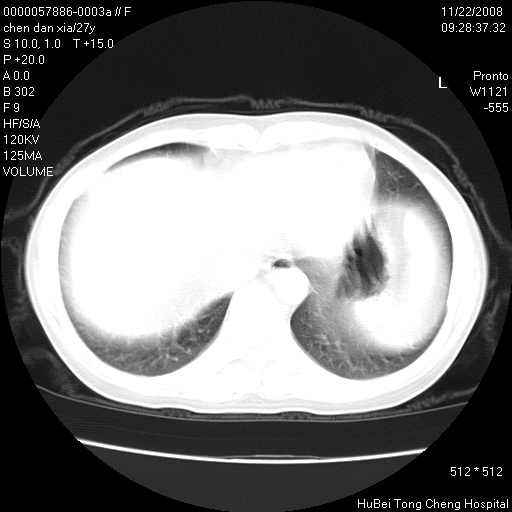

标题: CT16752:F,27Y。发热咳嗽20余天,伴盗汗。 [打印本页]

标题: CT16752:F,27Y。发热咳嗽20余天,伴盗汗。

右下肺见片絮状影,两肺野内分布不均的小结节影,结核并肺内播散可能性大,建议结合实验室检查 .

右下肺纹理模糊;纵隔可见肿大淋巴节;右心缘旁结节,边缘光滑,纵隔窗病变范围较肺窗明显小,首先考虑右下肺结核,不排外淋巴瘤

双肺纹影普多,部分呈网状,支炎或淋巴管炎?

局部胸膜增厚

右侧前胸壁胸膜局限性肥厚(胸膜炎?)其他的强化观察.

下肺结节,结节内钙化,肺门纵隔淋巴肿大 结核可能性大

1)考虑两肺感染性病变。2)纵隔淋巴结肿大。